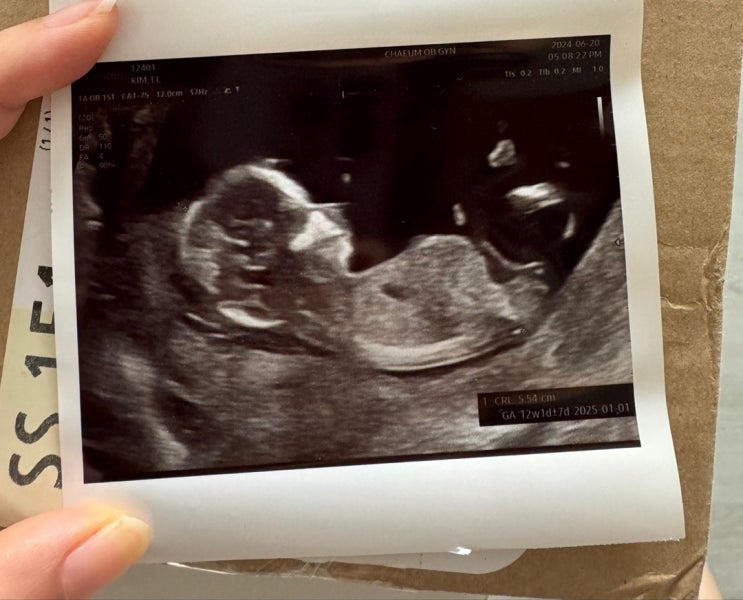

18주 강남차병원 전원 초진 후기~

2주만에 보러가는 햄! 초진은 어짜피 서로 알아가는 수준 같아서 18주에 초진을 잡았다.(한 달 전쯤 전화로...

12주 햄이맘은 성별 추측중... (1차 기형아 검사/ 장꾸맘)

현충일 쯤이었나..? 어느 날 입덧약 먹고 자는걸 깜박했는데 다음 날 완전 멀쩡하길래... 그 날 부로 입덧...